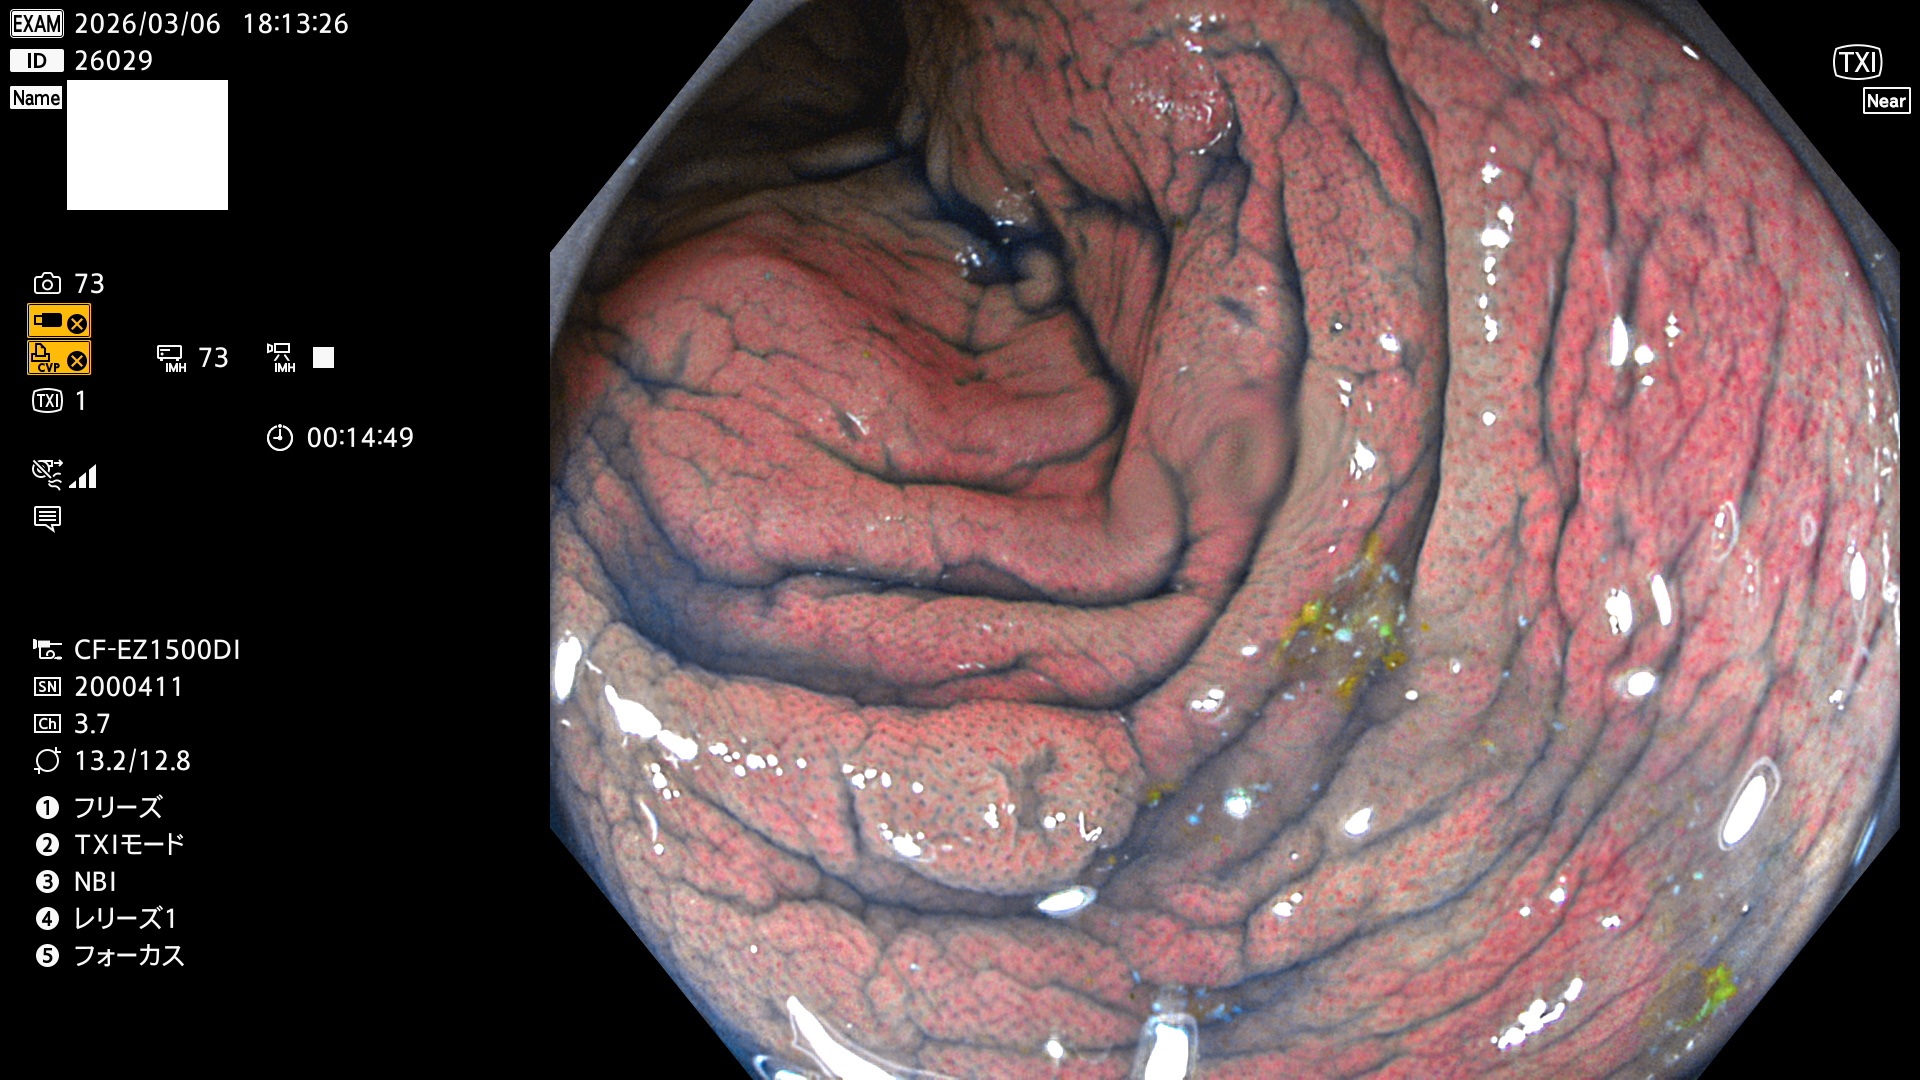

完全に平坦な物をUb、陥凹している物をUcと呼びます。Ubは認識が困難で、Ucはびらん(炎症)と紛らわしいために見落とされやすく、「内視鏡後・大腸癌」の原因になります。

専門的)Uc=De Novo癌? 内視鏡の解像度が低かった時代、このような説もありました。しかし今日の高精度内視鏡では良性の微小なUc型腺腫(APC遺伝子異常の腺腫)が日常的に見つかります。Ucこそが多段階発癌(Adenoma-Carcinoma Sequence)のMain Routeです。

毎週の検査(木・金・土・日)に発見されたUbとUc型・腺腫を、その週の日曜の夜にUPし1週間、提示します。

2026年3月5日〜3月8日の4日間(40件)9個 (Uc_ADR=9個/40人=23%)